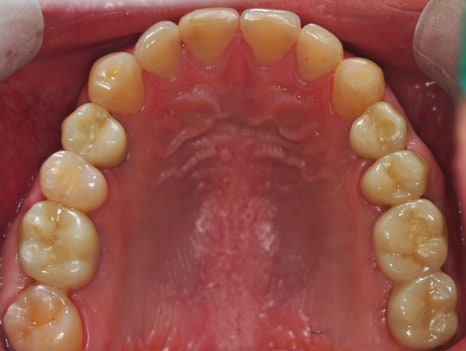

치료가 완료된 구강 사진을 보도록 하겠습니다.

▲치료 완료 후 파노라마 사진

이렇게 치료 최종 치료 기간까지는 23. 8월~24. 7월에 마무리하셔서 거의 1년 정도 소요가 되었습니다.